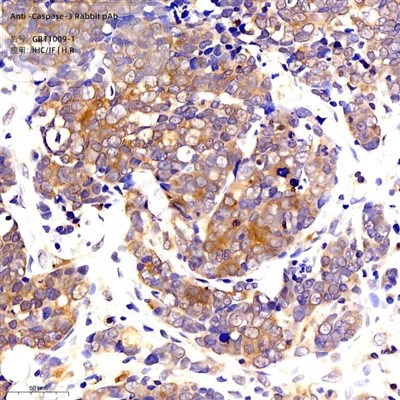

Immunohistoquímica de la parafina Incrustada amígdina humana mitjançant CD3 (GB11014) a la dilució de 1: 1000 (lent 400x) |

Immunohistoquímica de la parafina Embedded Mouse Spleen mitjançant CD3 (GB11014) a dilució de 1: 1000 (lent 400x) |

Immunohistoquímica de la parafina Esplenitis de ratolí incrustat mitjançant CD3 (GB11014) a dilució de 1: 1000 (lent 400x) |

Immunohistoquímica de la parafina Embedded Spleen mitjançant CD3 (GB11014) a dilució de 1: 1000 (lent 400x) |